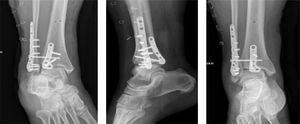

Al día siguiente del diagnóstico, el paciente ingresa a pabellón en donde se realiza una reducción abierta y osteosíntesis con placas y tornillos a través de un abordaje posterolateral logrando la desimpactación del fragmento proximal de la fíbula y osteosíntesis tanto de la fíbula como del maléolo posterior, además de la fijación sindesmal con tornillo bajo confirmación de la posición del material de osteosíntesis con visión fluoroscópica. Luego, a través de un abordaje medial se realiza la reducción y osteosíntesis del maléolo medial con tornillos canulados (figura 5).

Radiografías de tobillo posterior a reducción y osteosíntesis. Radiografía de tobillo. Proyección en mortaja, lateral AP, luego de reducción y osteosíntesis de luxofractura de tobillo mostrada en la figura 4.